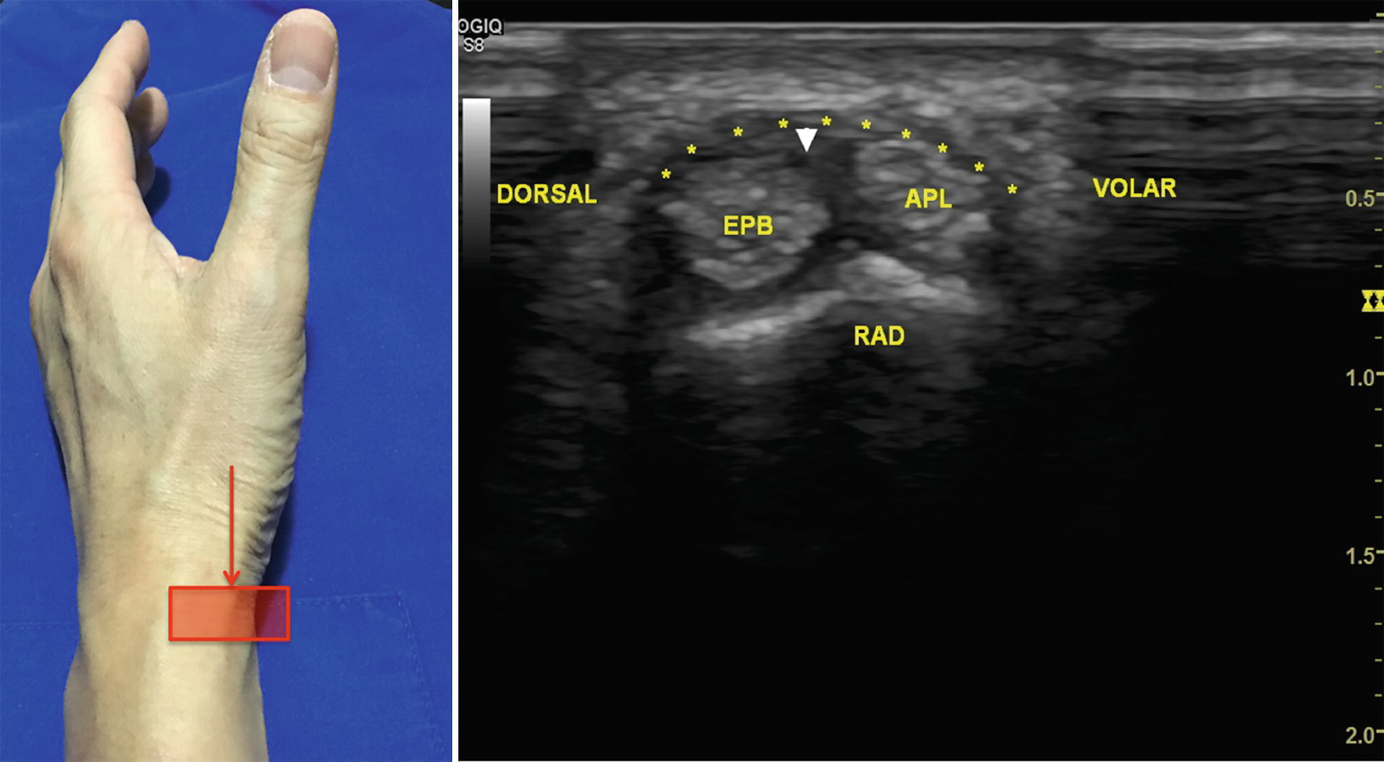

Pdf Thumb Ultrasound Technique And Pathologies

Pdf Thumb Ultrasound Technique And Pathologies from www.researchgate.net